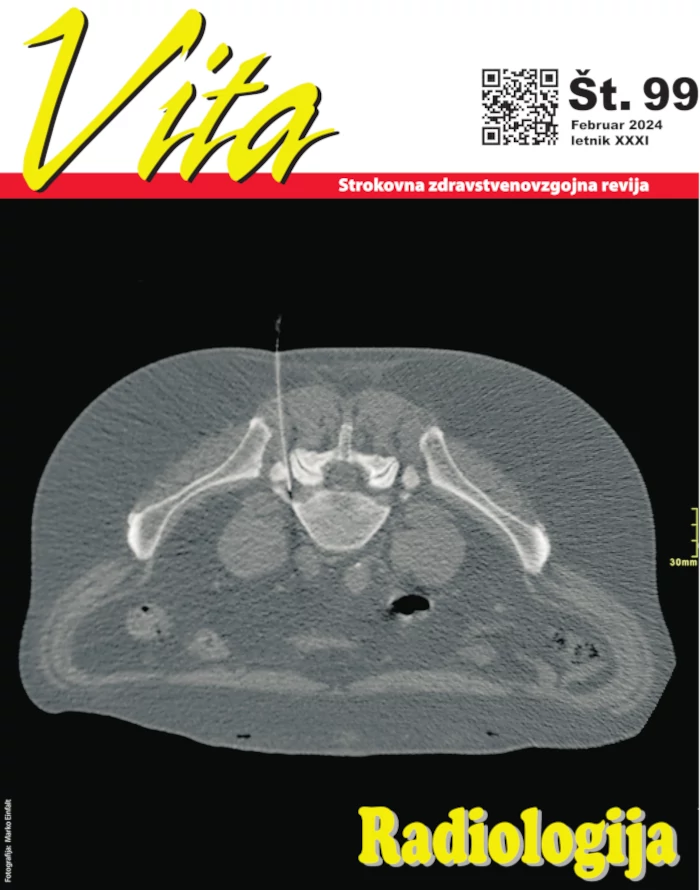

Radiologija

(Februar 2024)

Timsko delo in medsebojno zaupanje v radiologiji

Osnove diagnostične radiologije

Osnove interventne radiologije

Neželeni učinki ionizirajočega sevanja na koži

Interventna nevroradiologija

Radiološki posegi mišično skeletnega sistema